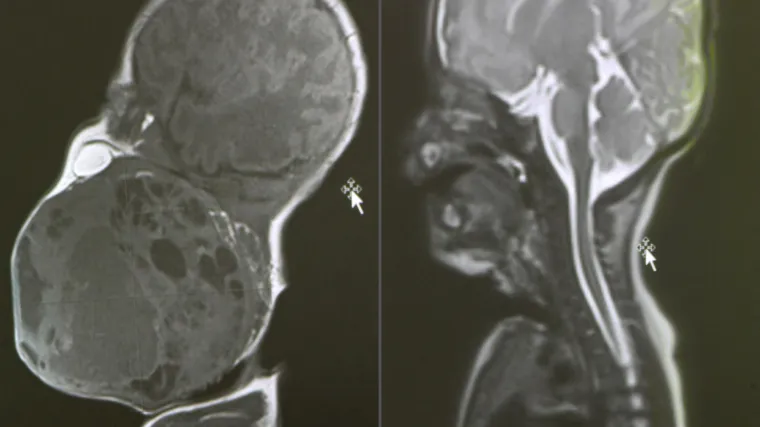

Prema nalazima magnetske rezonance prije poroda, tumor je bio gotovo veličine djetetove glave i zatvarao je dišne puteve. Dijete bi bilo životno ugroženo ako bi se rodilo normalnim putem, stoga je tim liječnika morao razraditi i biti spreman na nekoliko varijanti liječenja, a na kraju je profunkcionirala prva opcija.

"Kada smo bili sigurni da smo uspostavili umjetno disanje preko tubusa koji je stavljen u dušnik, tada smo rekli - idemo poroditi dijete. Dijete je izvađeno kompletno izvan maternice, podvezana je pupkovina i nakon što smo ga stabilizirali, istoga dana je učinjeno kompletno odstranjenje tumora s obzirom na to da smo nekoliko sati nakon samog poroda primijetili u intenzivnoj da se tumor povećava", rekla je Grizelj.

Voditelj Odjela za fonijatriju Ratko Prstačić pojasnio je da je patohistološka dijagnoza pokazala da se radi o teratomu, generalno dobroćudnom tumoru, ali s potencijalnom malignom opasnošću pa će dijete trebati onkološko praćenje, no druga terapija trenutačno nije potrebna.